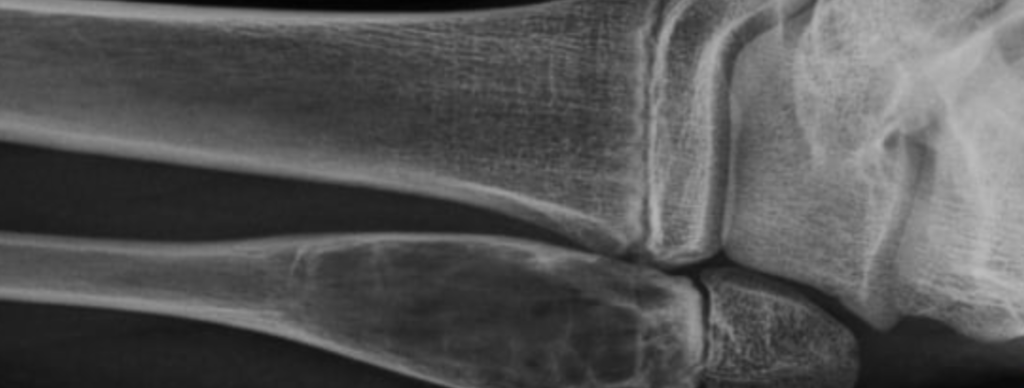

Fratura fechada

Fratura deslocada

Fratura articular

Fratura subperiostal

Fratura frisária